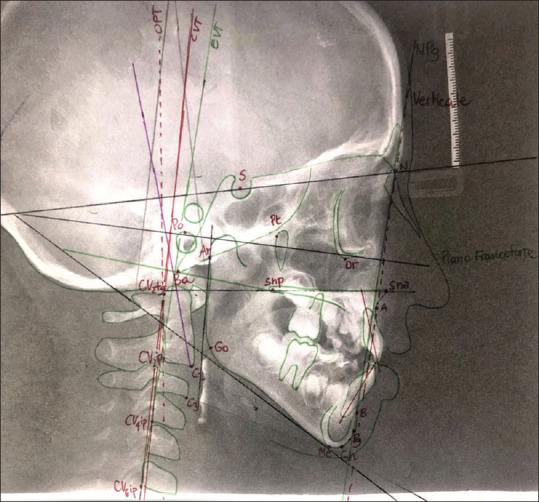

MATERIALS AND METHODS

A consecutive series of 35 subjects, aged between 6 and 14 years, with no prior history of orthodontic treatment, and requiring skeletal expansion of the upper arch, were selected and analyzed. All patients were treated with REP or Mcnamara appliance: the active phase of 15 days and retaining phase of 6 months. Cephalometric analysis was carried out before (T0) and after (T1) orthodontic therapy evaluating changes in the craniofacial area and those related to CCP. The obtained data were statistically analyzed for the pre-post changes.

No statistically significant difference emerged indicating a modification in the CCP measured at T0 and T1 ( > 0.05). Patients treated with the McNamara appliance, compared to those treated with REP, showed a higher value of the angle OPT ^ Ver ( = 0.021), and a lower measure of the angles CVT^EVT ( = 0.035) and EVT^Ver ( = 0.023). Furthermore, patients treated with REP showed a higher hyoid angle value than those treated with McNamara ( = 0.047).

选取并分析了连续35例年龄在6至14岁之间、无前正畸治疗史且需要上颌骨扩弓的受试者。所有患者均接受REP或麦克纳马拉矫治器治疗:激活期15天,保持期6个月。在正畸治疗前(T0)和治疗后(T1)进行头影测量分析,评估颅面部区域的变化以及与CCP相关的变化。对获得的数据进行前后变化的统计学分析。

结果

在T0和T1测量的CCP变化方面,未出现具有统计学意义的差异(>0.05)。与接受REP治疗的患者相比,接受麦克纳马拉矫治器治疗的患者OPT^Ver角的值更高(=0.021),CVT^EVT角(=0.035)和EVT^Ver角(=0.023)的测量值更低。此外,接受REP治疗的患者舌骨角值高于接受麦克纳马拉矫治器治疗的患者(=0.047)。